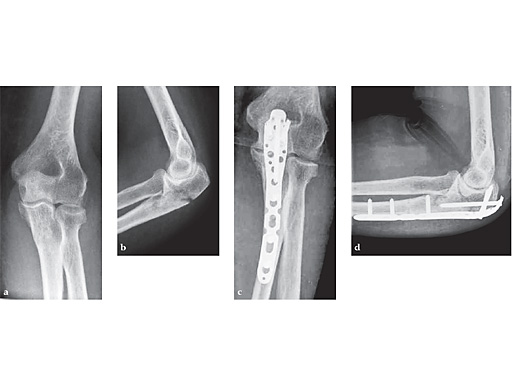

65-year-old female treated with an Olecranon plate.

ab Preoperative x-rays.

cd Postoperative x-rays.